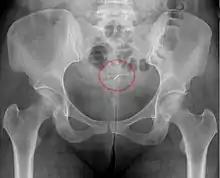

![]() Correctly inserted IUD | |